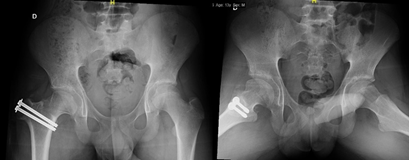

A 12-year-old male patient, who began medical controls in our service in 2018, diagnosed with Legg-Calvé-Perthes disease of the right hip (Figure 1), presenting pain when standing, agitated gait, and claudication. In 2022 in tomographic control (Figure 2) and CT with 3D reconstruction (Figure 3) that evidence right coxa magna and alteration of the femoral sphericity with CAM type morphology, associated with pain and limitation of range of motion, was the reason for which it was decided to perform surgical intervention. Physical exam: Pain and limitation of range of motion (right/left flexion 100°/100°, right/left internal rotation 28°/45°, right/left external rotation 12°/20°, limited abduction due to pain in the right lower extremity).

Figure 2 Computed Axial Tomography of the hip from the year 2022, showing evidence of the right coxa magna and alteration of the femoral sphericity of CAM type morphology.

2. Computed Axial Tomography of the hip from the year 2022, showing evidence of the right coxa magna and alteration of the femoral sphericity of CAM type morphology.